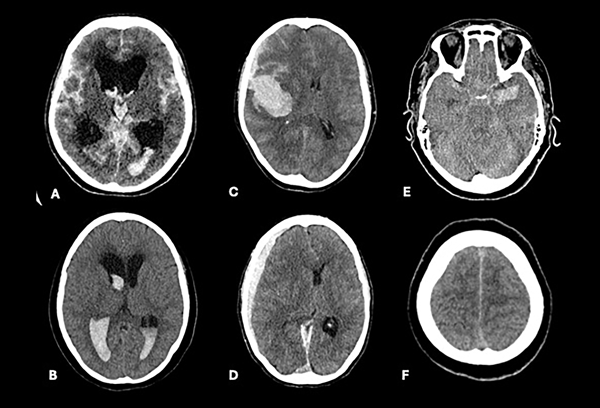

Otras variables analizadas fueron la presencia de hidrocefalia (índice de Evans >0.3), hematomas (con efecto de masa o volumen >30 cm3) y edema cerebral (desviación de línea media, borramiento de surcos, compresión de cisternas basales en ausencia de hidrocefalia o hematoma) como signos de hipertensión endocraneana. El resangrado se definió como deterioro clínico asociado con aumento de sangrado intraparenquimatoso, subaracnoideo o intraventricular en tomografía (Figura 1). Se evaluaron signos de herniación cerebral analizando alteraciones pupilares como la presencia de anisocoria pupilar, midriasis bilateral o III par craneal por compresión directa. A su vez, se clasificó el tiempo desde el sangrado al tratamiento quirúrgico en 3 categorías: a) <24 horas, b) de 24-72 horas, c) >72 horas.

Figura 1. A y B) Hidrocefalia y Fisher 4. C y D) Hematoma con efecto de masa. E y F) Edema cerebral con compresión de cisternas basales y surcos de la convexidad.